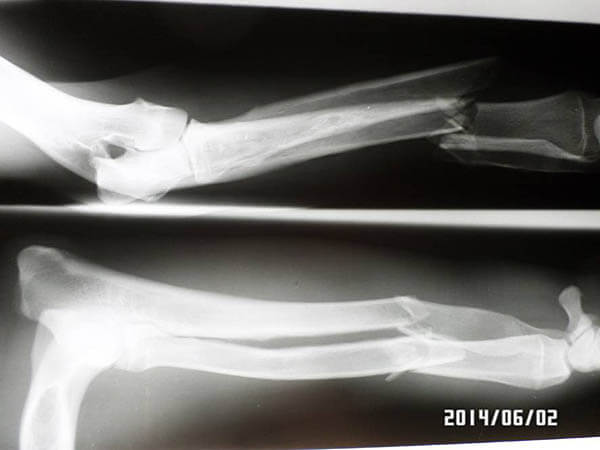

Diese sehr dünne Doggen-Hündin namens Ghost wurde am 27.5.14 schwer verletzt gefunden und dem Tierheim gemeldet. Vermutlich wurde sie angefahren. Ein Bein ist gebrochen und dazu hat sie noch diverse andere Verletzungen. Sie ist jetzt in tierärztlicher Behandlung und wir hoffen fest, dass sie wieder gesund wird und dann ein liebevolles Zuhause findet! Zur Zeit ist sie verständlicherweise noch sehr verstört und ängstlich. Ihr Blick zeugt von viel Leid….

Am 2.6.14 wurde Ghost operiert! Wir hoffen auf schnelle Genesung und danach auf ein Zuhause!